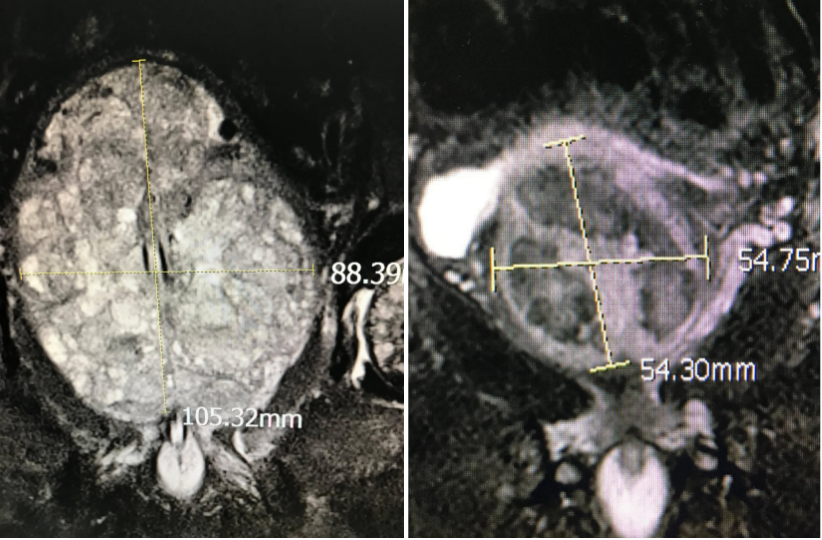

图:通过栓塞增生部分萎缩(图为栓塞前和栓塞后一个月的对比)